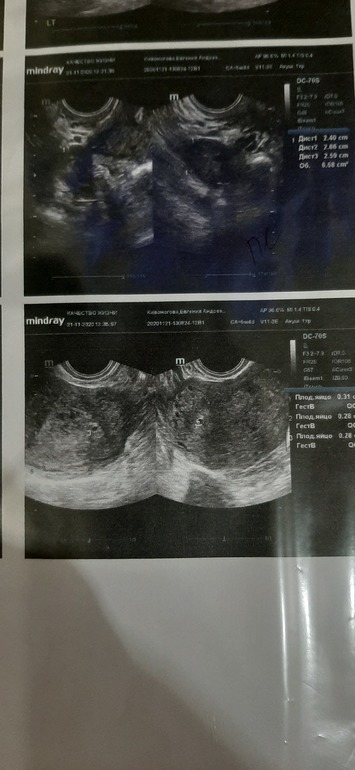

Женечка в Дневник Зачатия 5 лет УЗИ в левой трубе в углу плодное яйцо но это не точно размер 2.9мм кто-нибудь сталкивался м таким диагнозом? Посмотрите еще 20 записей на эту тему Отменить Ответить Тест на беременность У кого была чистка вакуумом? Чаты Беременных Выберите чат: Январята-2026 Февралята-2026 Мартята-2026 Апрелята-2026 Майчата-2026 Июнята-2026 Июлята-2026 Августята-2026